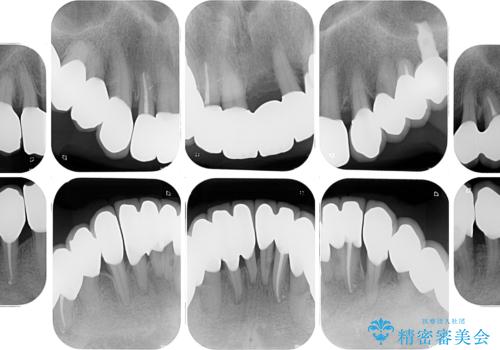

歯周病でグラグラの歯 矯正治療と歯周外科を併用した総合歯科治療

- 近医に通い続けるも、一向に不快感が改善しないとのことで来院された患者様です。

診察を行ったところ、重度歯周病の状態の上に上下の歯列が著しい叢生という状態でした。

歯周初期治療として抜歯や歯槽骨再生治療を行い、さらに歯周ポケット除去を行った後に矯正治療で歯列を整えて行くこととしました。

2~3年は早く終了する予定でしたが、途中で体調を崩されて来院されない時期が続いたため、非常に長期間の治療となりました。

上顎口蓋からの堅い歯肉を移植する角化歯肉移植術を行いたかったのですが、体調不良から実施しなかったため、最終補綴物であるオールセラミッククラウンを装着した後に、知覚過敏や境目が見てしまうといった問題が一部で発生いたしました。

最終的には痛みや違和感のない状態にて治療を終えることができました。